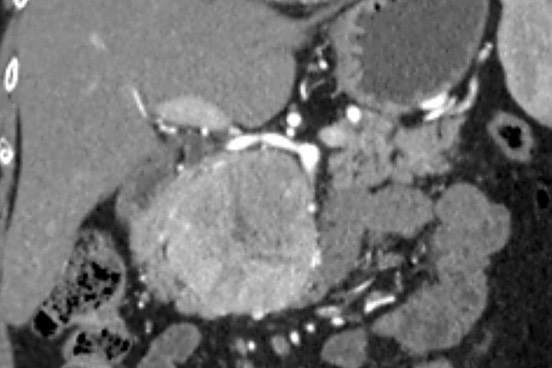

«Միքայելյան» համալսարանական հիվանդանոցում հերթական բարդ վիրահատությունն է իրականացվել, հեռացվել է ենթաստամոքսային գեղձի գլխիկի մեծ ուռուցք ավելի քան 10սմ տրամագծով, որը սերտ հպված էր միջընդերային զարկերակին և երակին:

Առհասարակ ենթաստամոքսային գեղձի գլխիկի մեծ չափի ուռուցքները համեմատաբար քիչ են հանդիպում: Առավել քիչ են հանդիպում այն դեպքերը, երբ գեղձի գլխիկի մեծ չափերի ուռուցքը չի առաջացնում մեխանիկական դեղնուկ: Համալսարանական հիվանդանոցի Վիրաբուժության կլինիկա է դիմել 62 տ. կին՝ գանգատվելով ցավից և ծանրության զգացումից վերորովայնային (էպիգաստրալ) շրջանում:

Հեռացված հյուսվածքի հետազոտությամբ հայտնաբերվել է ենթաստամոքսային գեղձի գլխիկի նեյրոէնդոկրին ուռուցք: